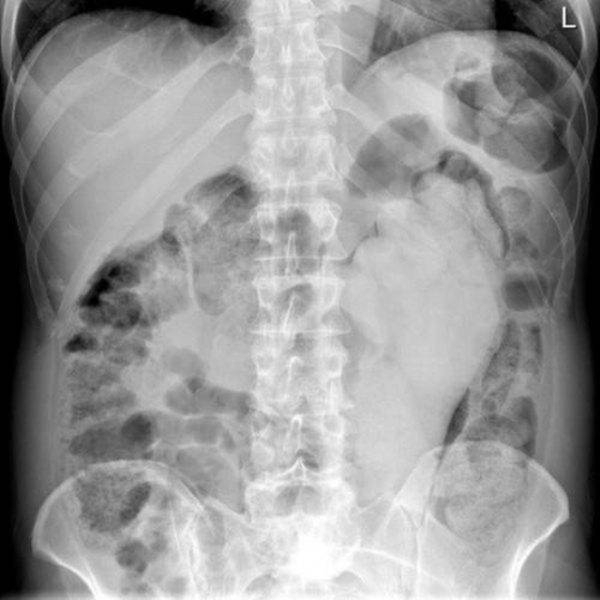

İÇİNDEKİ ŞEYE RÖNTGEN UZMANLARI ŞOK OLDU!

RÖNTGEN UZMANLARI ŞOK OLDU!

,Dünyada çekilen bu röntgenler hem röntgen uzmanlarını hemde görenleri şok ediyor...